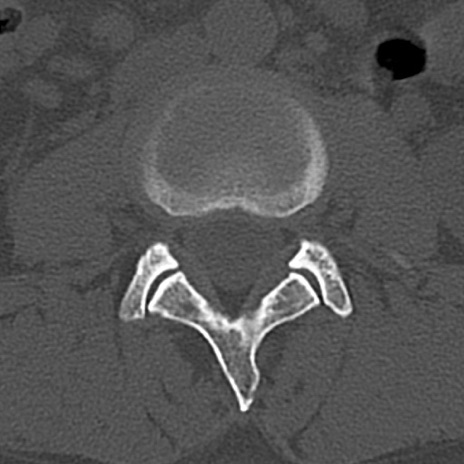

腰椎CT

横断像と矢状断像